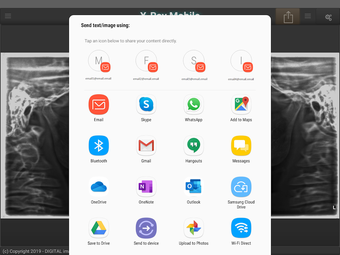

X-Ray Mobile is an Android app that allows users to acquire x-ray images directly on their mobile device. This app is especially useful for those in the medical field who need to take x-rays on the go. With X-Ray Mobile, users can also capture pictures from their camera and send them to a connected PC. The app uses WiFi to connect to the PC, making it easy to transfer images quickly and efficiently.